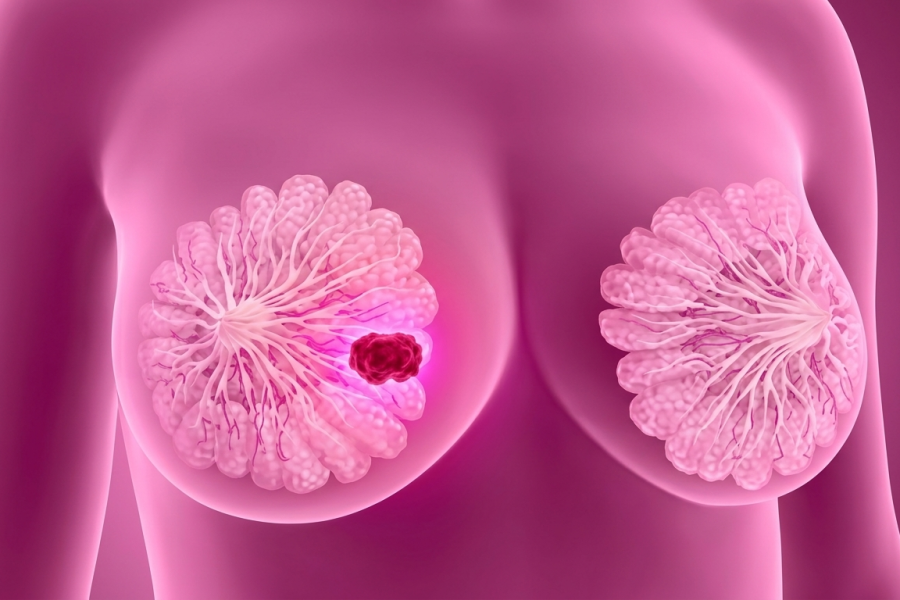

Acreditamos que quanto mais informação, maiores são as chances de um diagnóstico precoce e melhores tratamentos.

O Portal Câncer de Mama Brasil é desenvolvido por um grupo de seis médicos mastologistas de vários estados do País que aceitaram o desafio de difundir informações atuais, detalhadas e de qualidade sobre os avanços no tratamento do Câncer de Mama para a população brasileira.